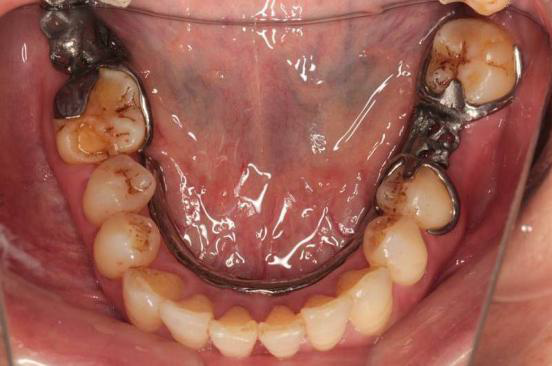

检查: 口腔卫生条件可,CI=1, DI=1,牙龈无充血肿胀,BOP(-),牙龈退缩约0.5~1mm,未探及深牙周袋,PD:3~4mm;口腔黏膜色性质正常, 舌体大小、形态、活动度正常。 36、47缺失,右侧下颌为游离端缺失,缺牙区近远中间隙及HE龈间隙可;剩余牙槽嵴吸收呈I型,高圆形;35、37牙体未见明显缺损,叩(-),松(-),46近中颊HE面有一大面积磨耗,探(-),叩(-), 松(-),上下前牙切端不同程度磨耗,并有不同程度的黄染,16远中HE面有一大面积黑色色素沉着,探(-),叩(-),松(-)

诊断:1. 下颌牙列缺损(Keneedy II类 I亚类) 2. 慢性牙周炎 处理: 取上下颌研究模型,行RPD设计, 根据设计进行牙体预备,取模,试戴钛支架,比色,试戴RPD,复查。